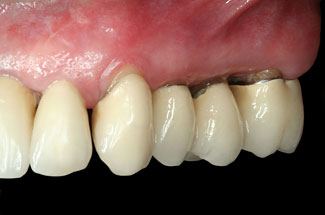

Abbildungen 3-5: Die klinischen Fotographien zeigen den Zustand nach der ersten professionellen Zahnreinigung.

Der komplexe Fall Der komplexe Fall

Abb. 3

Abb. 4